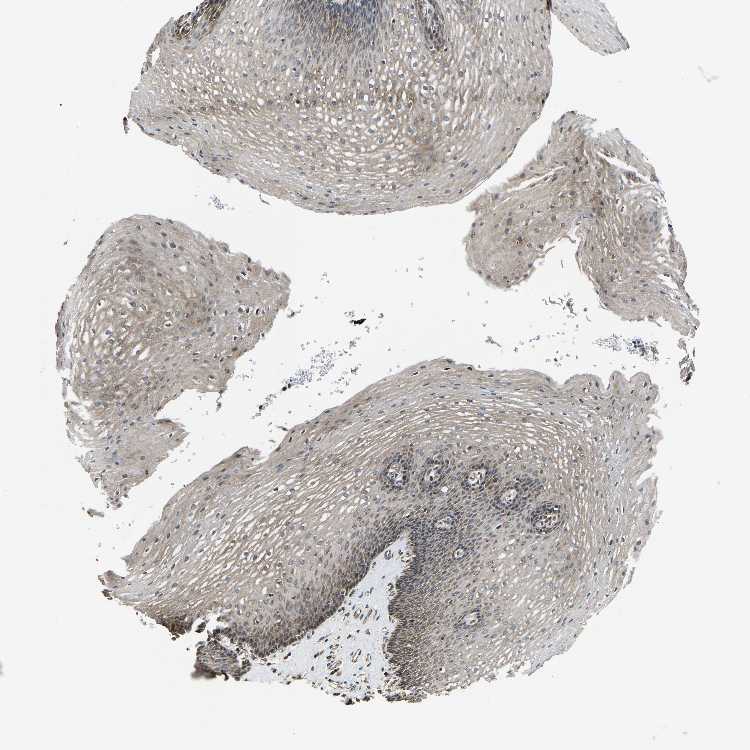

ESOPHAGUS - Antibody stainingi

Antibody staining in the annotated cell types in the current human tissue is reported as not detected, low, medium, or high, based on conventional immunohistochemistry profiling in selected tissues. This score is based on the combination of the staining intensity and fraction of stained cells.

Each image is clickable and will lead to virtual microscopy that enables deeper exploration of all samples and also displays staining intensity scores, fraction scores and subcellular localization as well as patient and tissue information for each sample.

Antibody HPA014536Antibody HPA019191

Squamous epithelial cells Not detectedMedium